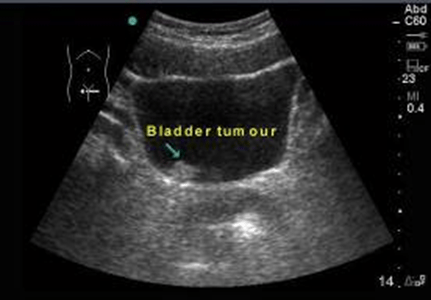

Images And Video Resources

Haematuria Clinic: Initial Consultation and Investigations